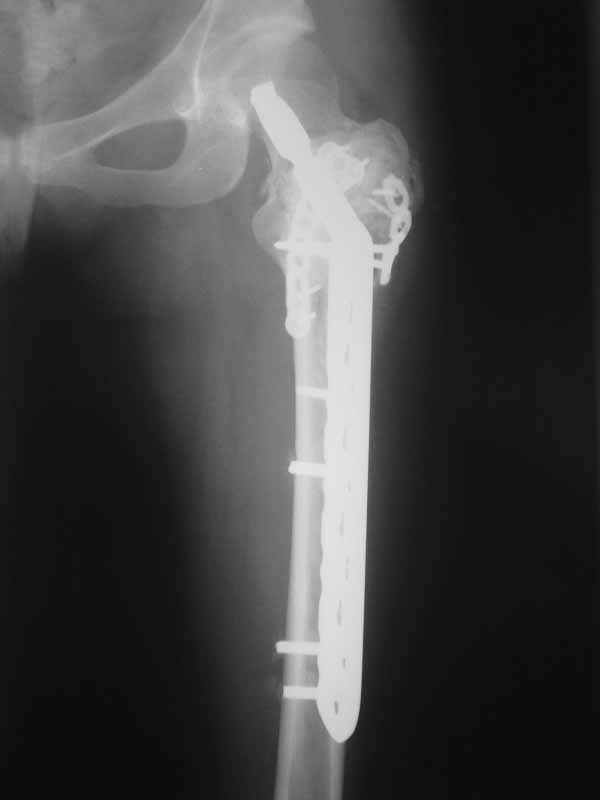

А по пациентке:Обследования провели в легких чисто, лабораторно - без особенностей. Выполнили МРТ - костная киста, однокамерная. Оперирована - створчатая остеотомия, удаление кисты, костная пластика аутокостью с гребня подвздошной кости, остеосинтез DHS со сприральным клинком, створка фиксирована пластинами монокортикально.

Макроскопически - слизеподобное содержимое темно-бурого цвета, отдали на гистологию.